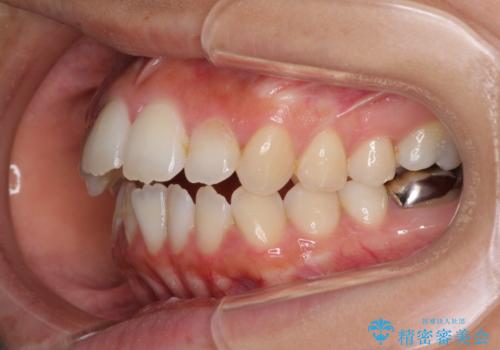

開咬と前突を改善 ワイヤー装置での抜歯矯正

元々むし歯の処置歯が多く、神経を取り除いている歯が多くありましたが、どうやら右上の前歯と小臼歯は外傷により神経を失った可能性があり、抜歯したスペース前後の歯が全く動かない状態でした。

結果として下顎の小臼歯は抜歯せず、右上の抜歯スペースはむし歯処置を兼ねてオールセラミックブリッジにて補綴治療を行うこととしました。

動かない歯での停滞や、出産と子育てなどにより治療期間は長期化しましたが、整った歯列にて仕上げることができました。